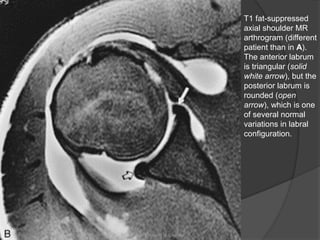

T1 fat-suppressed

axial shoulder MR

arthrogram (different

patient than in A).

The anterior labrum

is triangular (solid

white arrow), but the

posterior labrum is

rounded (open

arrow), which is one

of several normal

variations in labral

configuration.